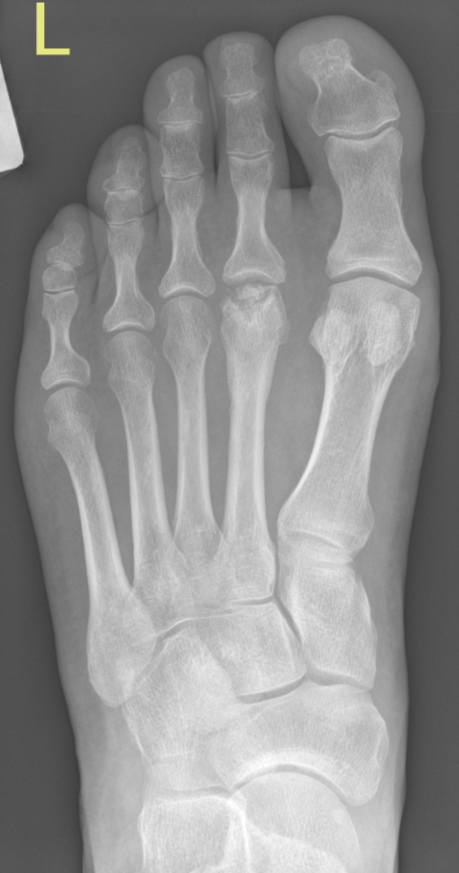

Freiburg osteonecrosis (AVN) of 2nd metatarsal head